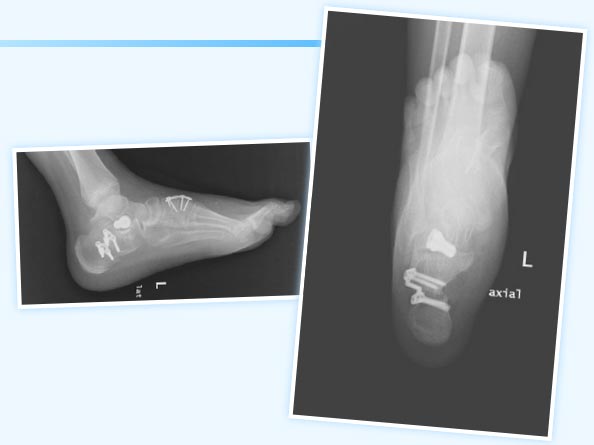

上圖為患者扁平足術(shù)后影像資料

術(shù)后小兒骨科按照術(shù)前制定的護(hù)理及康復(fù)方案,從術(shù)后傷口護(hù)理、體位護(hù)理、下床訓(xùn)練、扶拐行走訓(xùn)練等各方面指導(dǎo)患者進(jìn)行康復(fù)。患者于近期治愈出院,現(xiàn)經(jīng)門診復(fù)診治療效果滿意。這是玉溪市中醫(yī)醫(yī)院完成的第一例復(fù)雜僵硬性扁平足手術(shù),標(biāo)志著我院治療青少年扁平足進(jìn)入了一個(gè)新的階段。